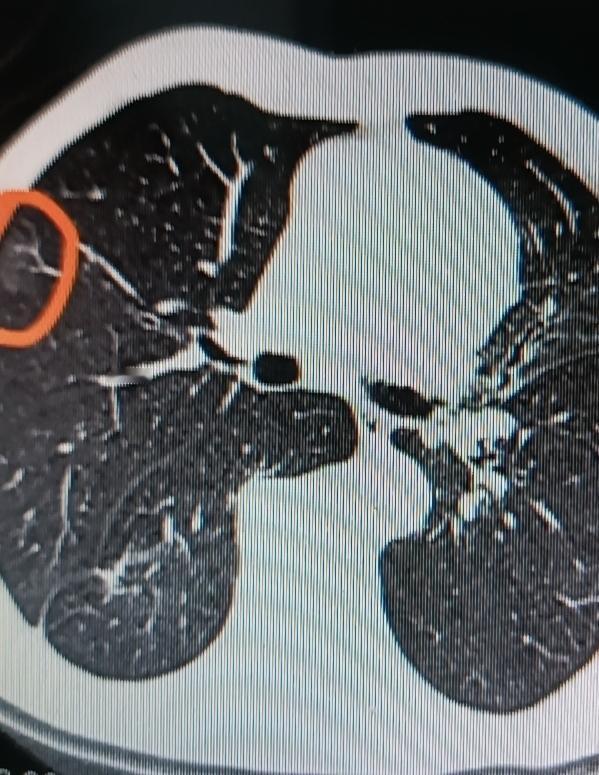

中老年人肺部出现磨玻璃阴影可别慌。磨玻璃阴影在CT影像上就像磨砂玻璃一样,密度轻度增高。 它可能是良性的,比如肺部炎症、出血等情况,经过治疗,炎症消退,阴影可能就没了。像肺炎引发的磨玻璃阴影,消炎后复查可能就消失了。 但也有恶性的可能,有可能是早期肺癌的表现。不过就算是早期肺癌,现在医疗技术也进步了,早发现早治疗,治愈希望很大。所以发现磨玻璃阴影,别自己吓自己,及时找医生进一步诊断才是关键。